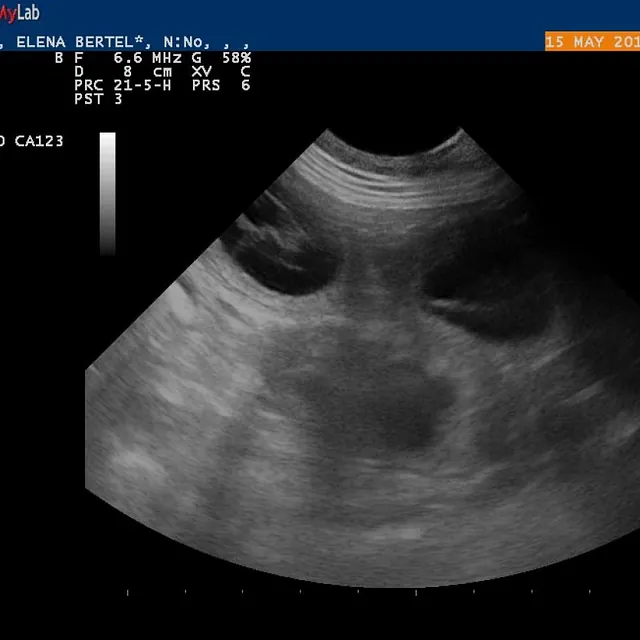

15.05.2017

Alice er drægtig!

e-kuld, 2017, sommer, kennel basta dog, schnauzere, schnauzerhvalpe, schnauzeropdræt, mellemschnauzer, alenzo, alice, hvalpe, købe schnauzer

Dejlig, dejlig nyhed!!!

Alice (Allegra)  er drægtig!

Scanning i dag har nemlig bekræftet den dejlige nyhed!

Hvor mange hvalpe er der inde? Tja, en del af dem kan du se på de billeder fra scanning :)

Nu krydser vi fingre for at alt går godt og vi får dejlige hvalpe efter de smukke og dygtige forældre!

P.S. Scaninngsbillederne ved klik på dem vil kunne ses i større størelse!